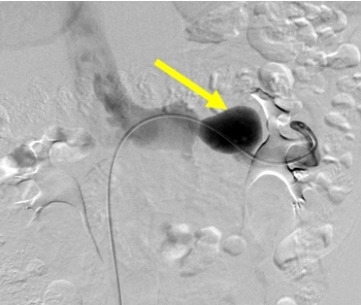

入院后,第一介入病房 外周血管介入病房副主任畅智慧为其进行了肾动脉和肾静脉血管造影检查,确认左肾静脉处存在一个约4cm的球状静脉瘤,并排除了胡桃夹综合征。